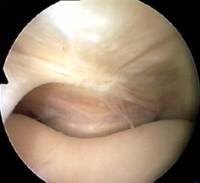

You will remember that so far I have taken you through the routine of starting with the arthroscope in the anterolateral portal (AL) and examining the medial side (as in the photo), then swapping it over to the anteromedial portal (AM) and examining the lateral side (link). From these two portals, much of the knee cavity can be viewed and probed.

I've mentioned plicae already on this course. Although a plica is a normal structure, some people have them and some don't. They may differ in situation, size and thickness. If a medial plica is abnormal and thickened it can often be felt as a string-like object to the inner side (medial) of the patella. From the suprapatellar portal it is amazing how easy it is to see why medial plicae cause pain.

Look again at this region but this time from the front and side (all the left knee).

It should be clear that from the usual anterolateral portal one cannot see much of what is going on in this suprapatellar area because the bulge of the rounded femur gets in the way.

Certainly one cannot appreciate the plica being nipped between patella and femur in the way that you can from above.